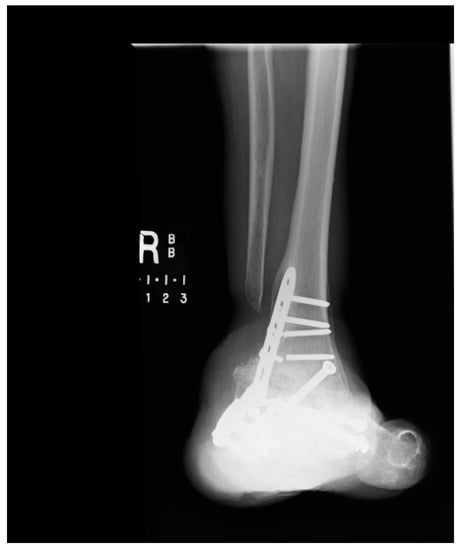

1.1.2. Operation

1.1.3. Post-Operative Follow-Up

1.1.4. Post-Operative Imaging